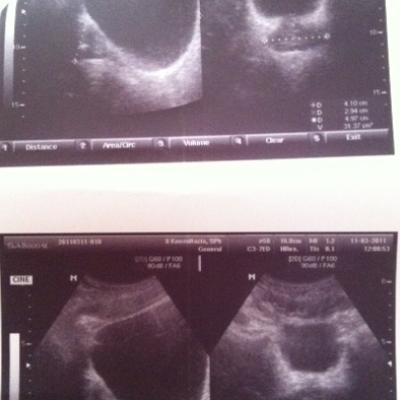

Добрый день! Дайте совет пожалуйста! Мне 30 лет. В декабре 2010 г. обнаружен хронический простатит, сделана узи, назначено лечение :

Псоле второго раза было сделано УЗИ, обнаружено образование камней.